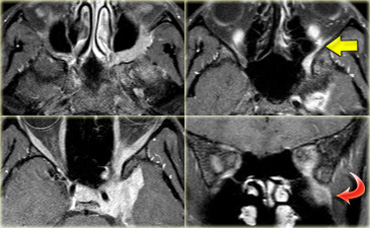

Schwannoma in CPA-region with typical features of an extraaxial tumor (T2WI) Schwannoma in CPA-region with typical features of an extraaxial tumor (T2WI)

The T2W-images show a schwannoma located in the cerebellopontine angle (CPA).

This case nicely demonstrates the typical signs of an extra-axial tumor.

There is a CSF cleft (yellow arrow).

The subarachnoid vessels that run on the surface of the brain are displaced by the lesion (blue arrow).

There is gray matter between the lesion and the white matter (curved red arrow).

The subarachnoid space is widened because growth of an extra-axial lesion tends to push away the brain.

All these signs indicate that this is a typical extra-axial tumor.

In the region of the CPA 90% of the extra-axial tumors are schwannomas.